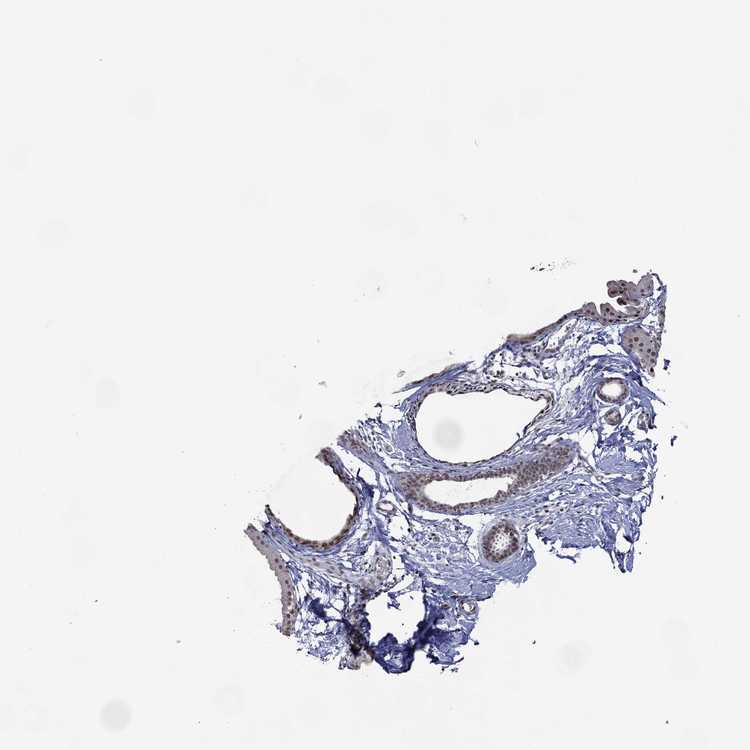

BREAST - Antibody stainingi

Antibody staining in the annotated cell types in the current human tissue is reported as not detected, low, medium, or high, based on conventional immunohistochemistry profiling in selected tissues. This score is based on the combination of the staining intensity and fraction of stained cells.

Each image is clickable and will lead to virtual microscopy that enables deeper exploration of all samples and also displays staining intensity scores, fraction scores and subcellular localization as well as patient and tissue information for each sample.

Antibody HPA074729

Adipocytes Not detected

Glandular cells Low

Myoepithelial cells Not detected